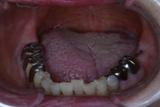

「8020運動」 表彰に出て頂いた方々のお口を拝見